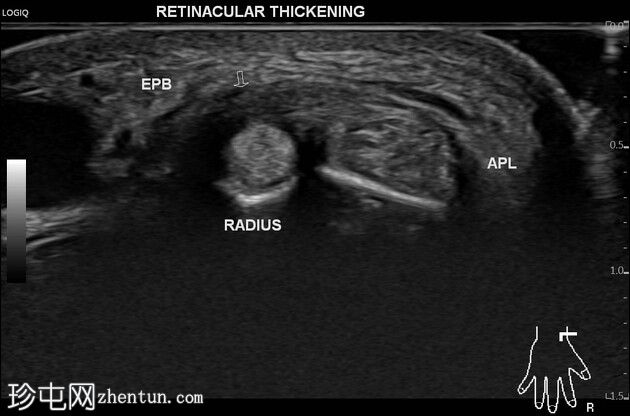

腕部拇短伸肌腱支持带增厚呈低回声。拇长展肌腱支持带未见增厚。两肌腱之间存在隔膜,止于桡骨皮质嵴。未见肌腱撕裂/腱鞘积液。

患者临床诊断为桡骨茎突狭窄性腱鞘炎(De Quervain腱鞘炎),超声检查证实了该诊断。超声检查还显示第一伸肌腱鞘两肌腱之间存在隔膜,以及拇短伸肌腱支持带选择性增厚。